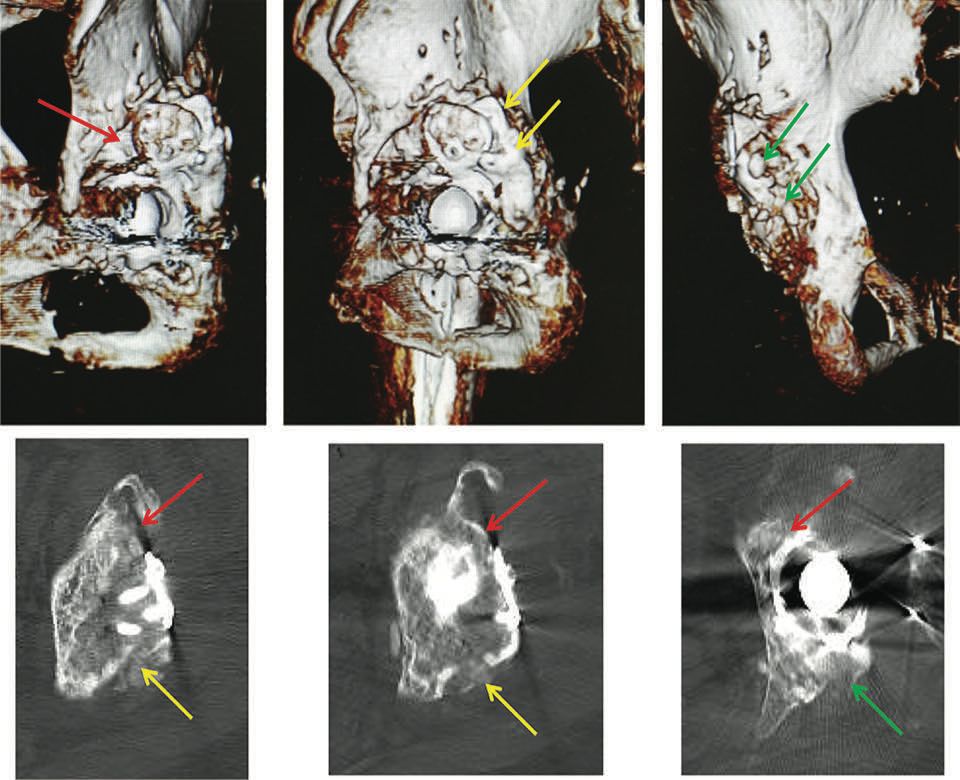

The video demonstrates the technique for reconstructing the acetabulum using an allograft and KT device (Fig. 16). It shows a two-stage revision hip replacement due to an infection. The bone defect was classified during the preoperative planning as AAOS III (combined defect).

Figures 17 and 18 show the preoperative x-rays and 3D CT images. The acetabulum was reconstructed using a KT cross and allografts.

The segmental and cavitary defects were successfully filled. Figures 19 and 20 show the postoperative images.